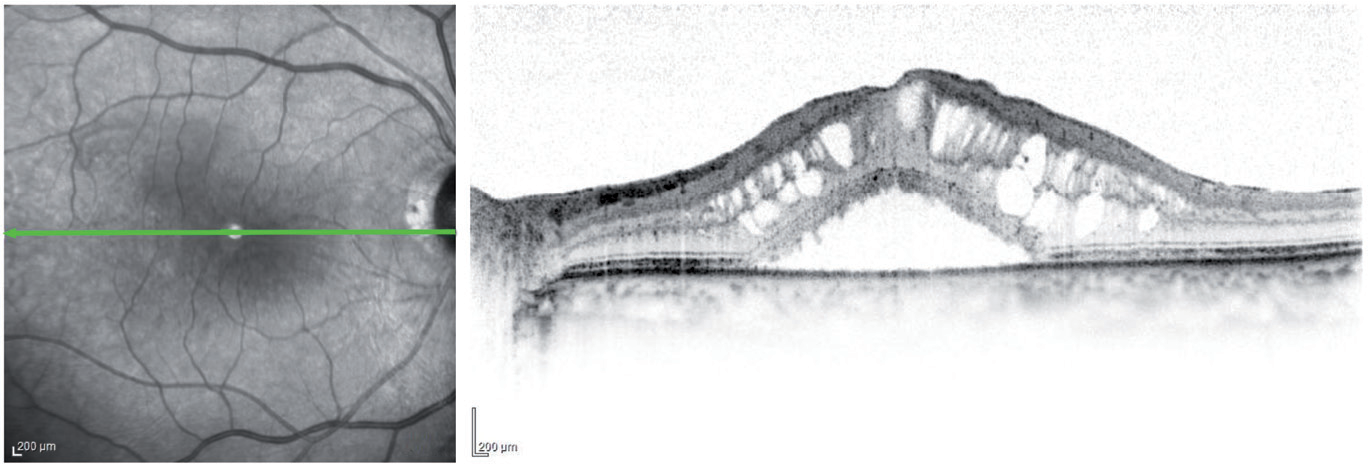

Tomografía de coherencia óptica (OCT, por sus siglas en inglés). La OCT es otra manera de observar en detalle la retina. Un equipo especializado analiza la estructura de la retina por medio de captura de imagenes en forma muy similar a tomar una fotografía y provee imágenes muy detalladas de su espesor. Esto ayuda al médico a detectar alguna fuga y medir la inflamación o edema de la mácula.